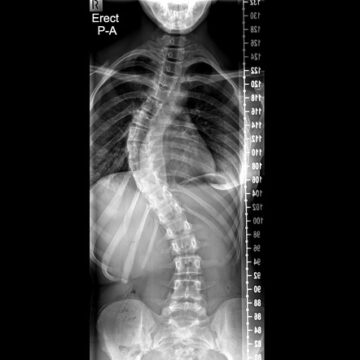

مارس 14, 2026 اعوجاج العمود الفقري لماذا يصبح أكثر تصلبًا مع الوقت؟ الأسباب والعلاج للأطفال… scoliosis, اعوجاج العمود الفقري, الجنف لا يوجد تعليق 75 المشاهدات اعوجاج العمود الفقري لماذا يصبح أكثر تصلبًا مع الوقت؟ الأسباب والعلاج للأطفال يعاني بعض الأطفال والمراهقين من اعوجاج العمود الفقري، وهو انحناء جانبي غير طبيعي للعمود الفقري يظهر خلال فترة النمو. وفي حالات كثيرة،